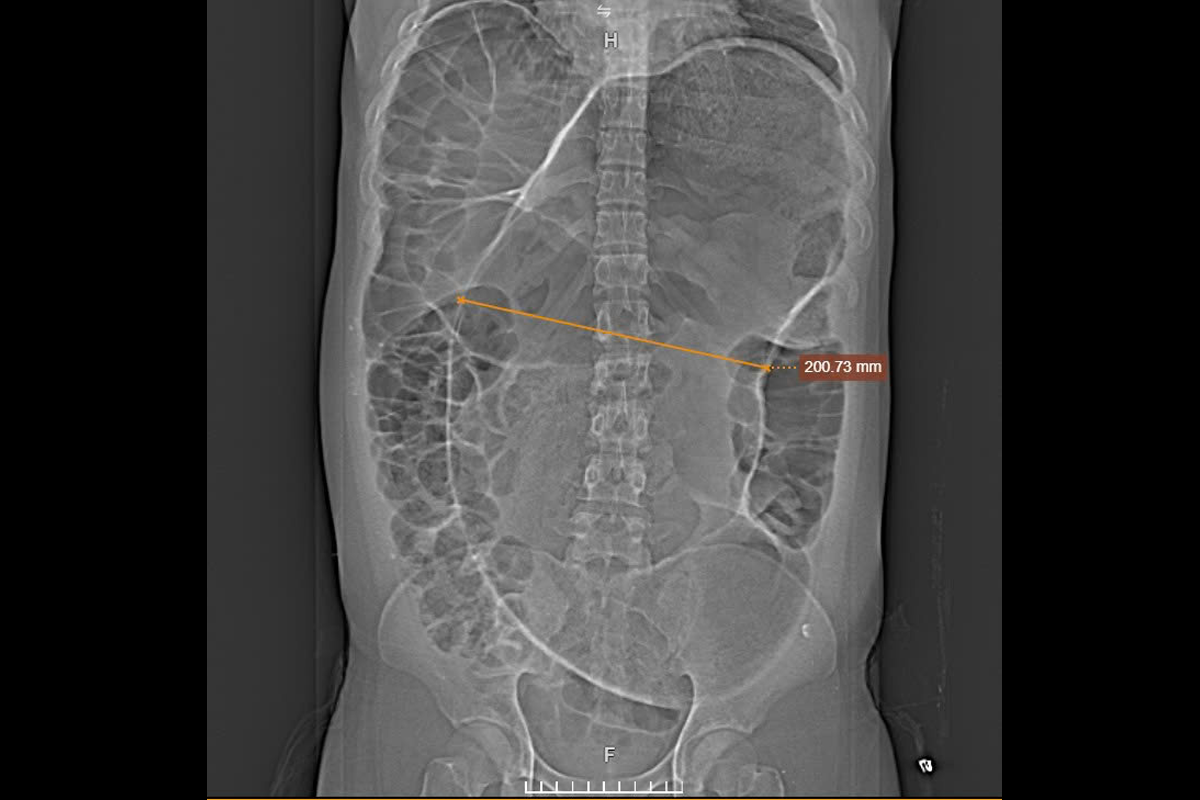

Previously, Minh suffered from constipation, which was treated with medication and a rectal tube. Three months later, his abdomen became severely distended, causing shortness of breath, abdominal pain, and an inability to eat, requiring nutritional infusions. A 1975-slice CT scan at Tam Anh General Hospital revealed sigmoid colon volvulus (the final segment of the large intestine), with the mesentery blood vessels and the sigmoid colon loop twisted, measuring 20 cm in diameter—nearly 7 times larger than normal. The intestinal lumen was filled with gas and waste, and the intestinal wall was thin.

Computed tomography showed the distended colon segment (yellow arrow). *Photo: Tam Anh General Hospital* |